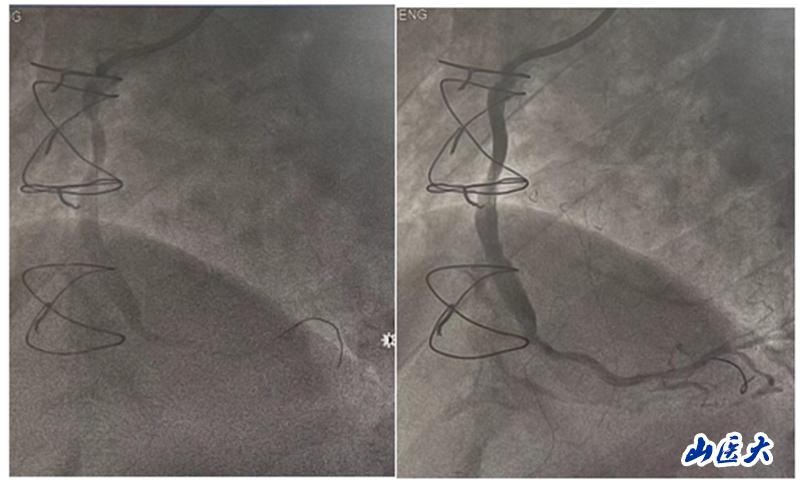

在手术中,团队发现患者的前降支、回旋支口部和右冠脉近段均存在闭塞情况,升主动脉-右冠脉桥血管近端狭窄约90%。团队决定对升主动脉-右冠脉桥血管进行介入治疗。他们快速准确地判断了病变血管的范围,并选择了激光消蚀辅助以及合适的球囊和支架进行干预治疗。手术后,患者安返病房,未再出现胸闷及气紧等不适症状。